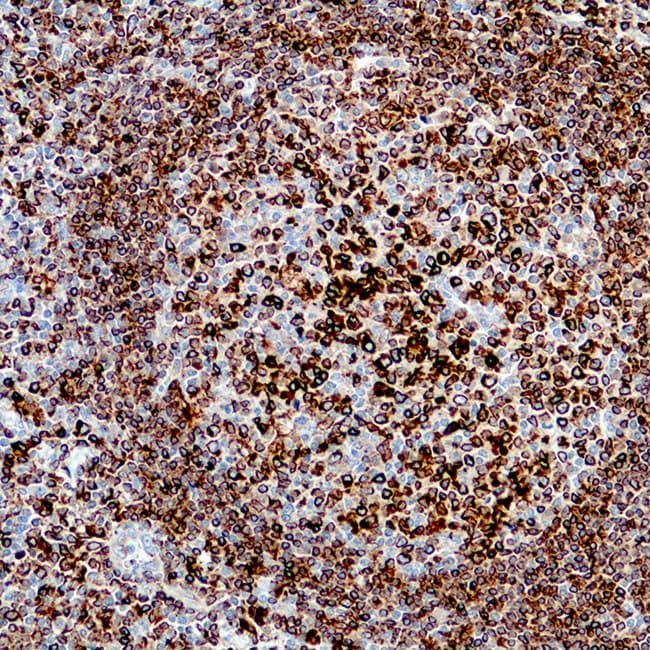

- Muestran una tinción membranosa y citoplasmática consistente con el tráfico intracelular de CD74.

- Proporcionan una detección sensible de las células presentadoras de antígenos y de los compartimentos ricos en células B.